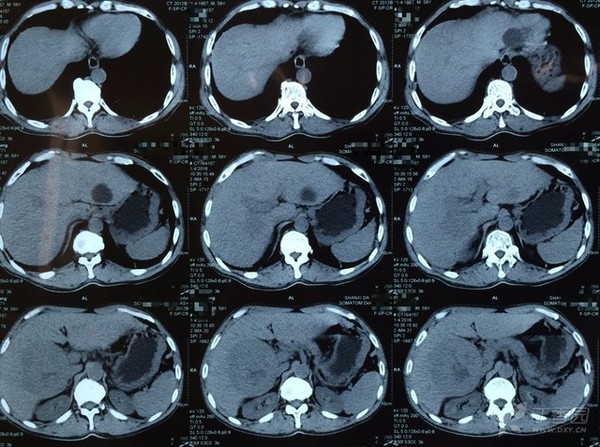

图 1 腹部 CT

CT 诊断意见:肝右叶占位伴出血,肝包膜下积液,考虑肝癌,肝左叶囊肿,胆囊壁水肿增厚,考虑继发性改变。